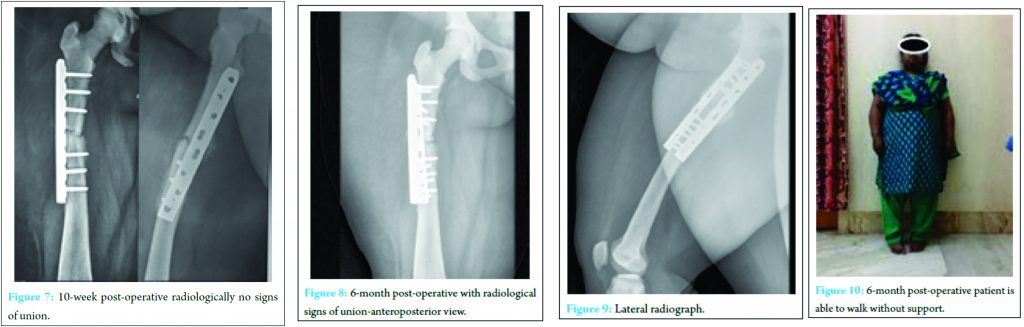

However, for this case, we preferred plate osteosynthesis because of the altered anatomy of the bone with a narrow medullary canal and severe osteosclerosis. Under Spinal anaesthesia, through lateral approach to the middle third of femur, a 12 cm incision was made. After deep dissection, fracture site was identified and exposed. After reducing fractures fragments an “8 holed broad dynamic compression plate with 3 proximal and 3 distal screws in compression mode was used for fracture fixation (Fig. 7).”

The difficulty encountered in the intra-operative period include, a difficulty in drilling the cortices and excess blood loss. The wound was closed in layers after adequate hemostasis. The immediate post-operative period was uneventful, and the patient discharged on the 14th post-operative day. The patient was discharged with advice of non-weight bearing walking with the help of walker support for minimum of 2 months and advised to review in the out-patient department for follow up every fortnight. At 10-week post-operative, after patient has been started on partial weight bearing walking, the patient reported with the complaints of pain over surgical site. On radiological examination, patient was found to have no signs of union at the fracture. Patient was immobilized for one month, but even after that, there were no signs of union. Hence, an additional stabilization procedure was done in the form of plating with autogenous cancellous bone grafting. Bone graft harvested from ipsilateral iliac crest was inadequate, and there was heavy bleeding from donor site so that an additional synthetic bone graft substitute was used. In the immediate post-operative period, patient developed deep seated infection which showed organism grown was staphylococcus aureus for which wound debridement was done. Patient was started on Intravenous antibiotics of Linezolid 600 mg twice a day after obtaining culture and sentivity report for period of 2 weeks, followed by oral antibiotics for 4 weeks. Patient was discharged 4 weeks later after complete subsidence of infection. Patient was advised physiotherapy in form of static and dynamic Quadriceps strengthening exercises,followed by hip and knee mobilization exercises and strict non weight bearing for 2 months. . At 3-month post-operative follow-up, there were signs of union clinically and radiologically (Fig. 8 and 9). The patient at present in the 6-month post-operative period with fracture united and on full weight bearing carrying out her daily activities without difficulty (Fig. 10).